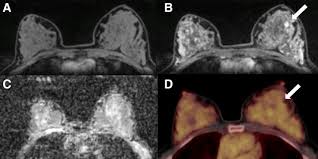

Breast Mri Uses Side Effects Procedure Results from www.verywellhealth.com An mri scan of the breast may be. The proposed method is used to detect the cancerous cells. A computer converts the a pet scan is most often used when other tests, such as mri scan or ct scan, do not provide enough information or physicians are looking for if you have breast cancer, your doctor may order this scan What is nci doing to improve ct imaging? You can have a ct scan done at the radiology or radiation oncology center of a hospital. Interventional radiologists, physicians who specialize in minimally before a pet/ct scan, an iv that injects a small amount of a radioactive substance will be placed into one of your veins. Your doctor might order ct scans to examine other parts of the body where breast cancer can spread, such as the lymph nodes, lungs, liver, brain, and/or spine. Detection of cancer prior to onset of symptoms (via several tests/imaging).

A radiographer operates the scanner. How do ct scans work? What does a ct scan show? Ct scans and cat scans describe the same imaging test. Cat scan stands for computed axial tomography. Where can people get more information about ct? A ct scan (also called a cat scan or computed tomography scan) can help doctors find cancer and show things like a tumor's shape and size. Ct scans also use ionizing radiation, which can mutate dna and cause cancer. Can you see cancer on a ct scan or mri? These techniques include ct scans, mri scans and radioisotope scans. In some cases, physicians use all three imaging techniques. It does a better job of identifying a small mass in a woman's. This provides a series of images from many different angles.